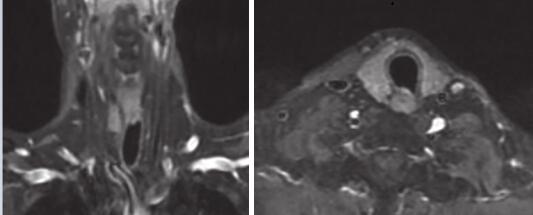

疗效评估:2疗程后靶病灶短径15.3mm→8mm,缩小 48%,评效 PR(图4)。4疗程及6疗程(图5)后评效维持PR。

图4 颈部增强MRI:2疗程后达PR

图5 颈部增强MRI:6疗程后靶病灶缩小为不可测量病灶,维持PR